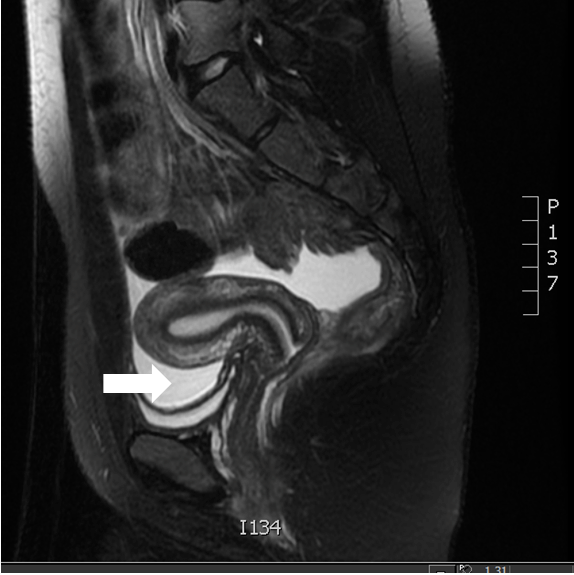

Nonetheless, despite the lack of abnormal findings (including papilledema), it was decided to perform a lumbar puncture, but not before performing an MRI/ MRV to rule out obstruction or stenosis of venous outflow like sagittal sinus thrombosis, which must be excluded before idiopathic intracranial hypertension can be diagnosed (Figure 2).

Figure 2: Brain MRI/MRV.

Share Image:

Our case demonstrates a patient with no remarkable past medical history (including no known history of prior headaches) and an adequate BMI who developed an intractable headache several weeks after starting medroxyprogesterone contraceptive injection hormone. The suspicion index for IIH was low given her adequate BMI (23.4 kg/m2). The first imaging study (head CT scan) was ordered to evaluate extra-axial fluid collection, midline shifting, amongst others, but instead, the official report described a partially empty sella turcica. This finding came as a surprise to the medical staff, as this is usually observed in overweight female patients. Additionally, the funduscopic examination performed by the ophthalmology staff came back negative.

Further evaluation with MRI/MRV was recommended, reporting findings compatible with IIH. Lumbar puncture showed marked elevated intracranial pressure, and there was a partial resolution of patient’s headache after the removal of 22 ml of spinal fluid. Patients with IIH have shown improvement with acetazolamide; our patient was discharged with said medication in combination with topiramate. After the discontinuation of the contraceptive method, the patient greatly improved her symptoms, even after she stopped taking the prescribed medications.

A patient with papilledema should have as soon as possible a head Ct or brain MRI (the preferred imaging study in IIH) which significantly increases the diagnosis of IIH if there is no intracranial occupying mass or a Dural sinus thrombosis [15]. MR venography is also useful particularly in patients at risk for Dural venous sinus thrombosis, those with hypercoagulative states, non-obese female, and male individuals. Extraluminal narrowing of the transverse sinuses may be one of the typical features of IIH [16].